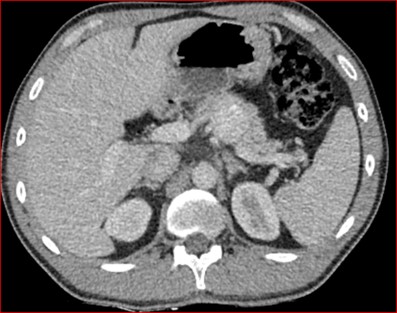

Se le practica una duodeno pancreatectomía cefálica y triple anastomosis (hepato yeyuno, gastroentero y wirsung enteroanastomosis) el 12 de octubre de 2023 y pasa a internación UTI, el 14 de octubre se complica con fiebre, dolor abdominal y fístula pancreática con dosaje de amilasa de drenaje >6000, por lo que se le realiza tomografía que muestra abundante líquido libre en cavidad. Por tal motivo se le realiza una exploración quirúrgica por laparotomía, encontrándose abundante líquido + pancreatitis en la anastomosis yeyuno pancreática. Se realiza lavado de cavidad + 3 drenajes abocados a zona pancreática + yeyunostomia.

Paciente que se intuba y pasa a UTI, posteriormente extubación exitosa. El 22 de octubre se complica con colección abdominal, por lo cual requiere de drenaje percutáneo guiado por TC.

Tomografía de abdomen y pelvis con cte ev: del 13/10/2023.

Complicaciones posquirúrgicas

Tomografía de abdomen con cte ev: del 20/10/2023.

Tomografía de abdomen con cte ev: del 26/10/2023.